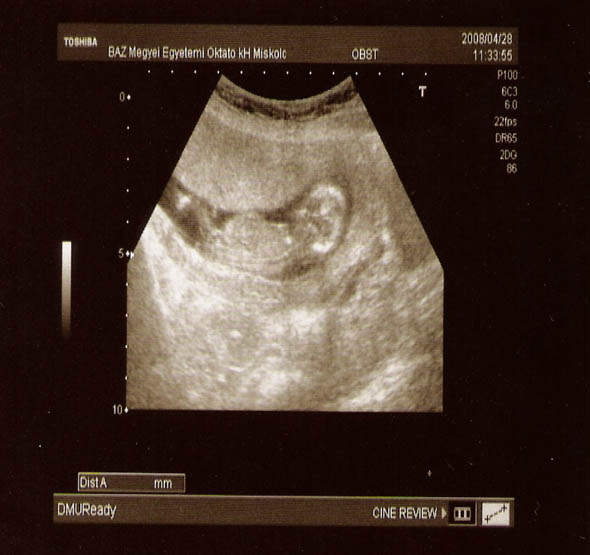

Minden ok velünk, 12 hetes UH-n már szép nagy 63 mm babót láttunk, aki kiintegetett, hogy szia anya! Olyan furi volt, hogy mellettem támaszkodott a Kornél, fennt meg lestük a picibabát! :)